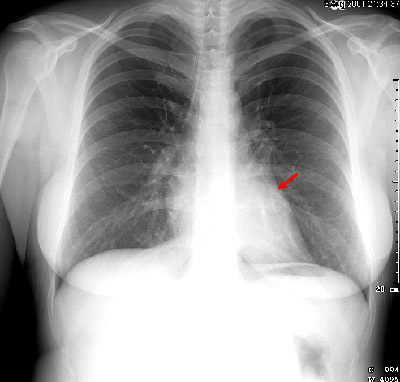

anatomical parts responsible for the cardiac contours on the PA chest film

anterior: Right heart border, left heart border, ascending aorta

posterior: Descending thoracic aorta, aortic knob (posterior portion of aortic arch)